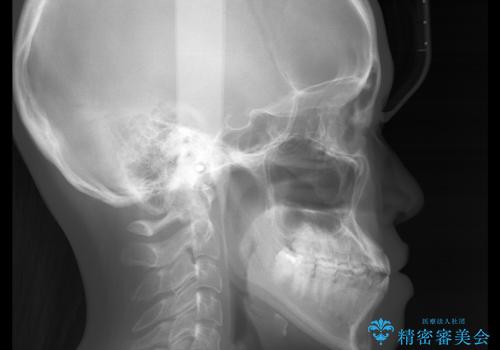

- やや受け口なのと、下の歯の隙間が気になるとのことで来院された患者様です。

また、オープンバイト(開咬)もありました。